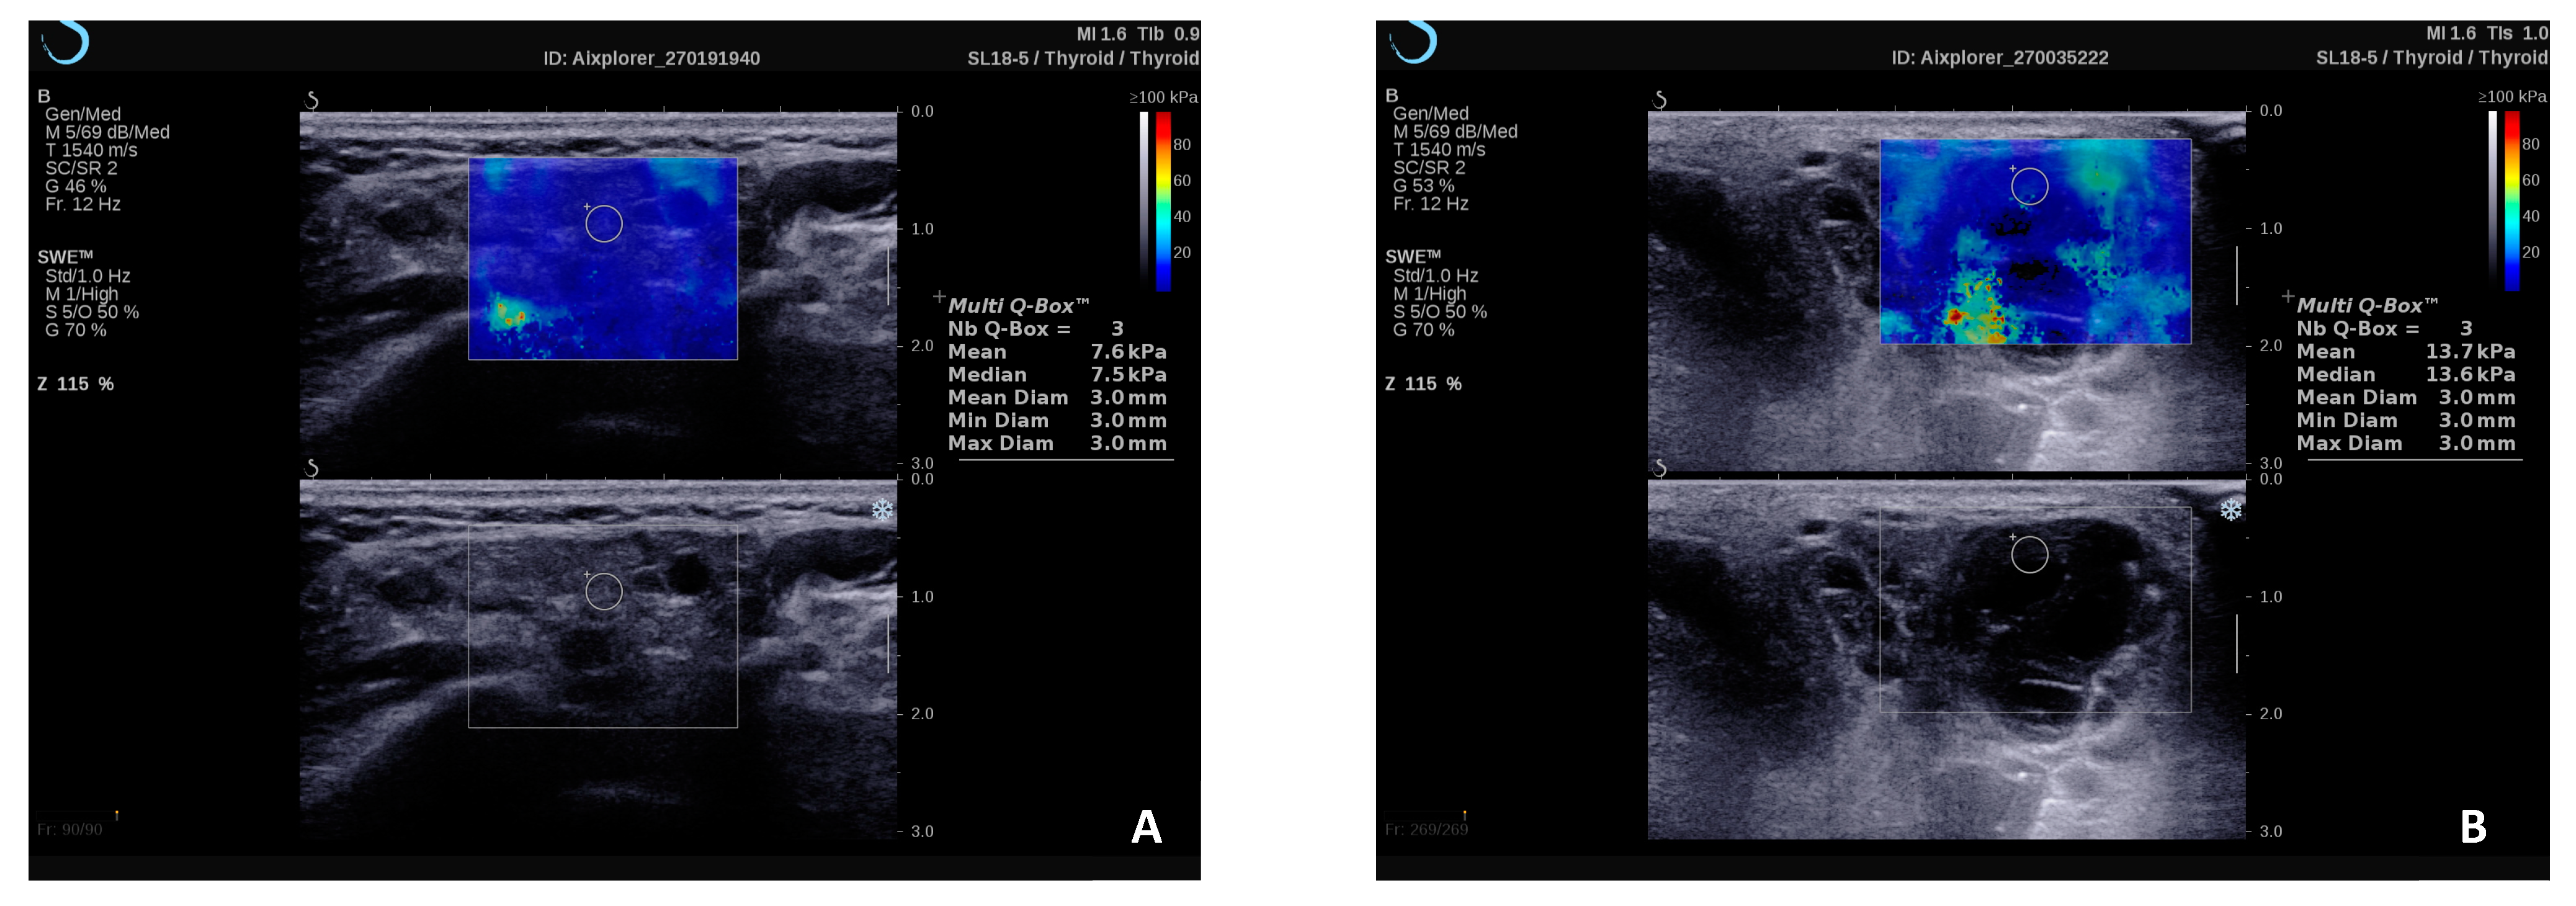

Notably, a recent study has emphasized the effectiveness of employing the 2D-SWE technique in a subgroup of patients who presented either normal (Grade 0) or inconclusive (Grade 1) features during the ultrasound B-mode MSG evaluation, which allowed the diagnosis of pSS with 94% sensitivity for the stiffness cut-off value of 6.45 kPa. [21]. Furthermore, within this same study, which included eight patients diagnosed with pSS-related MALT lymphoma, the authors noted that the combination of Grade 3 findings in ultrasonography (indicating > 50% hyperechoic bands), along with parotid hypertrophy and elasticity values exceeding 11.5 kPa, exhibited 100% specificity for MALT lymphoma, while maintaining a high level of sensitivity (92%) [23]. Figure 3 shows increased SWE values in the parotid gland parenchyma of a patient with pSS and lymphoma versus a patient with pSS without lymphomatous proliferation.

Figure 3.

2D-SWE examination of the parotid gland in a patient with pSS without lymphomatous proliferation (A) and a patient with pSS and associated MALT lymphoma that demonstrates higher stiffness values (B).